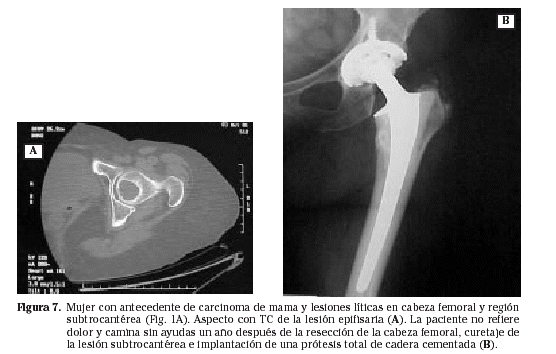

El planteamiento cambia en las lesiones epifisarias y metafisarias. La osteosíntesis pierde eficacia y es sustituida por las prótesis6 (Fig. 7). En la afectación predominantemente epifisaria, la solución es su resección con colocación de una prótesis articular convencional cementada, tanto en la cadera50 como en el hombro18. El cemento y el empleo de vástagos largos sirven para prevenir las consecuencias de la aparición posterior de otros focos. Si hay una afectación metafisaria amplia, que va a requerir de una resección ósea también amplia, en el defecto óseo se emplean bien prótesis especiales de resección o aloinjertos óseos compuestos: prótesis más injerto56.